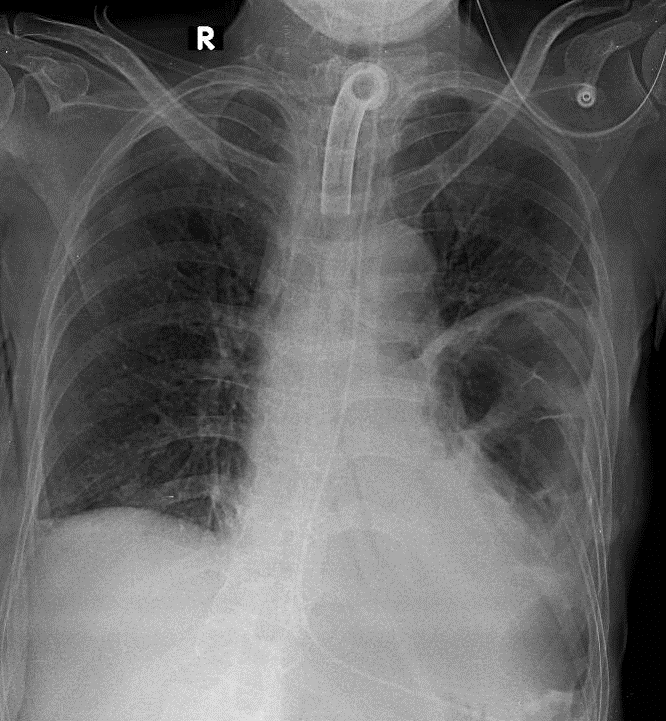

1-Có mở khí quản ra da, đang đặt canule 2-Tổn thương phế nang thùy dưới phổi trái kèm nhiều bóng khí, có tạo nhiều vách bên trong, không ghi nhận mực nước hơi, phần tổn thương nằm chồng lên hình ảnh bóng tim trái => Viêm phổi hoại tử, abcess phổi, .. 3-Tràn dịch màng phổi hai bên lượng ít làm mờ góc sườn hoành 4- có đặt ống sonde dạ dày, nằm đúng vị trí